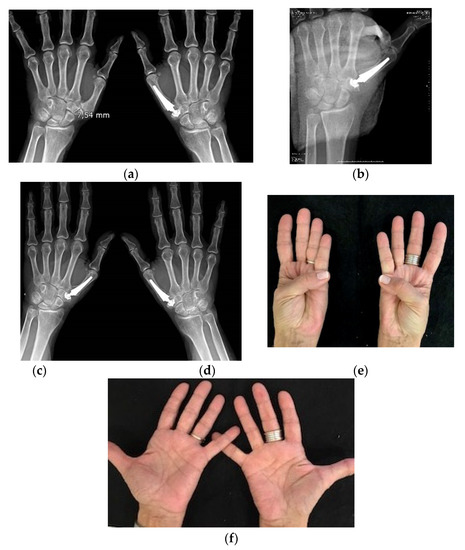

Radiological assessment was performed in 45 (92%) of functional joints. Of these, 39 (87%) showed good implant integration without any loosening. Six (13%) presented some ectopic calcification and slight radiolucency, but these were not associated with any adverse symptoms. The mean distance from the cup bottom to the scaphoid trapezium trapezoid joint was 4.4 mm (SD 1.6). Radiological implant positioning was better in the 26 prostheses that had been inserted using the current technique versus the original technique, and the differences were statistically significant. There was a lower incidence of oblique misalignment of the stem in PA XR view i.e., 12 (41%) for the original technique vs. two (8%) for the current technique (p < 0.001); implant subluxation occurred in 7 (22%) vs. 3 (6%), respectively, (p < 0.05); and cup subsidence occurred in 6 (21%) vs. 1 (4%), respectively, (p < 0.005). Figure 2.

It is remarkable the frequency of small trapeziums (defined as height in the radiographic projection PA < 9 mm) in the failed cases (4 out of 5) was much higher than in patients with functional outcomes (9 out of 50).

When analyzing the causes of prostheses failure, we find two main causes. A small trapezium was present in 80% of the failed prostheses and only in 18% of functional prostheses. Brutus y Kinen, in 2004 reported similar findings [34]. This does not prevent the use of prosthesis in those cases, but a special caution must be adopted during previous XR studies and in the surgical procedure in patients with a small trapezium. Figure 2. The preoperative first metacarpal adduction and the laxity of the metacarpo–phalangeal joint associated with TMCOA also contribute considerably to the failure with prosthetic dislocation or subluxation, as also was reported by Badıa and Sambandam (2006) [35]. Therefore, the prosthesis and these MP associated alterations must be treated at the same surgery to avoid complications.

Figure 2. (a) 67 year-old patient with bilateral trapeziometacarpal arthrosis. She has had an Arpe prosthesis on the right side for four years. She underwent surgery for prosthesis placement on the left side, where a small trapezium of 7.5 mm was observed; (b) Postoperative X-ray control. In a small trapezium there is enough space to place a cup with certainty if good planning and surgical technique are used; (c,d) AP and oblique X-ray control of both hands with 11 years of evolution on the left side and 15 years of evolution on the right side; (e,f) Thumb mobility at the last follow-up.